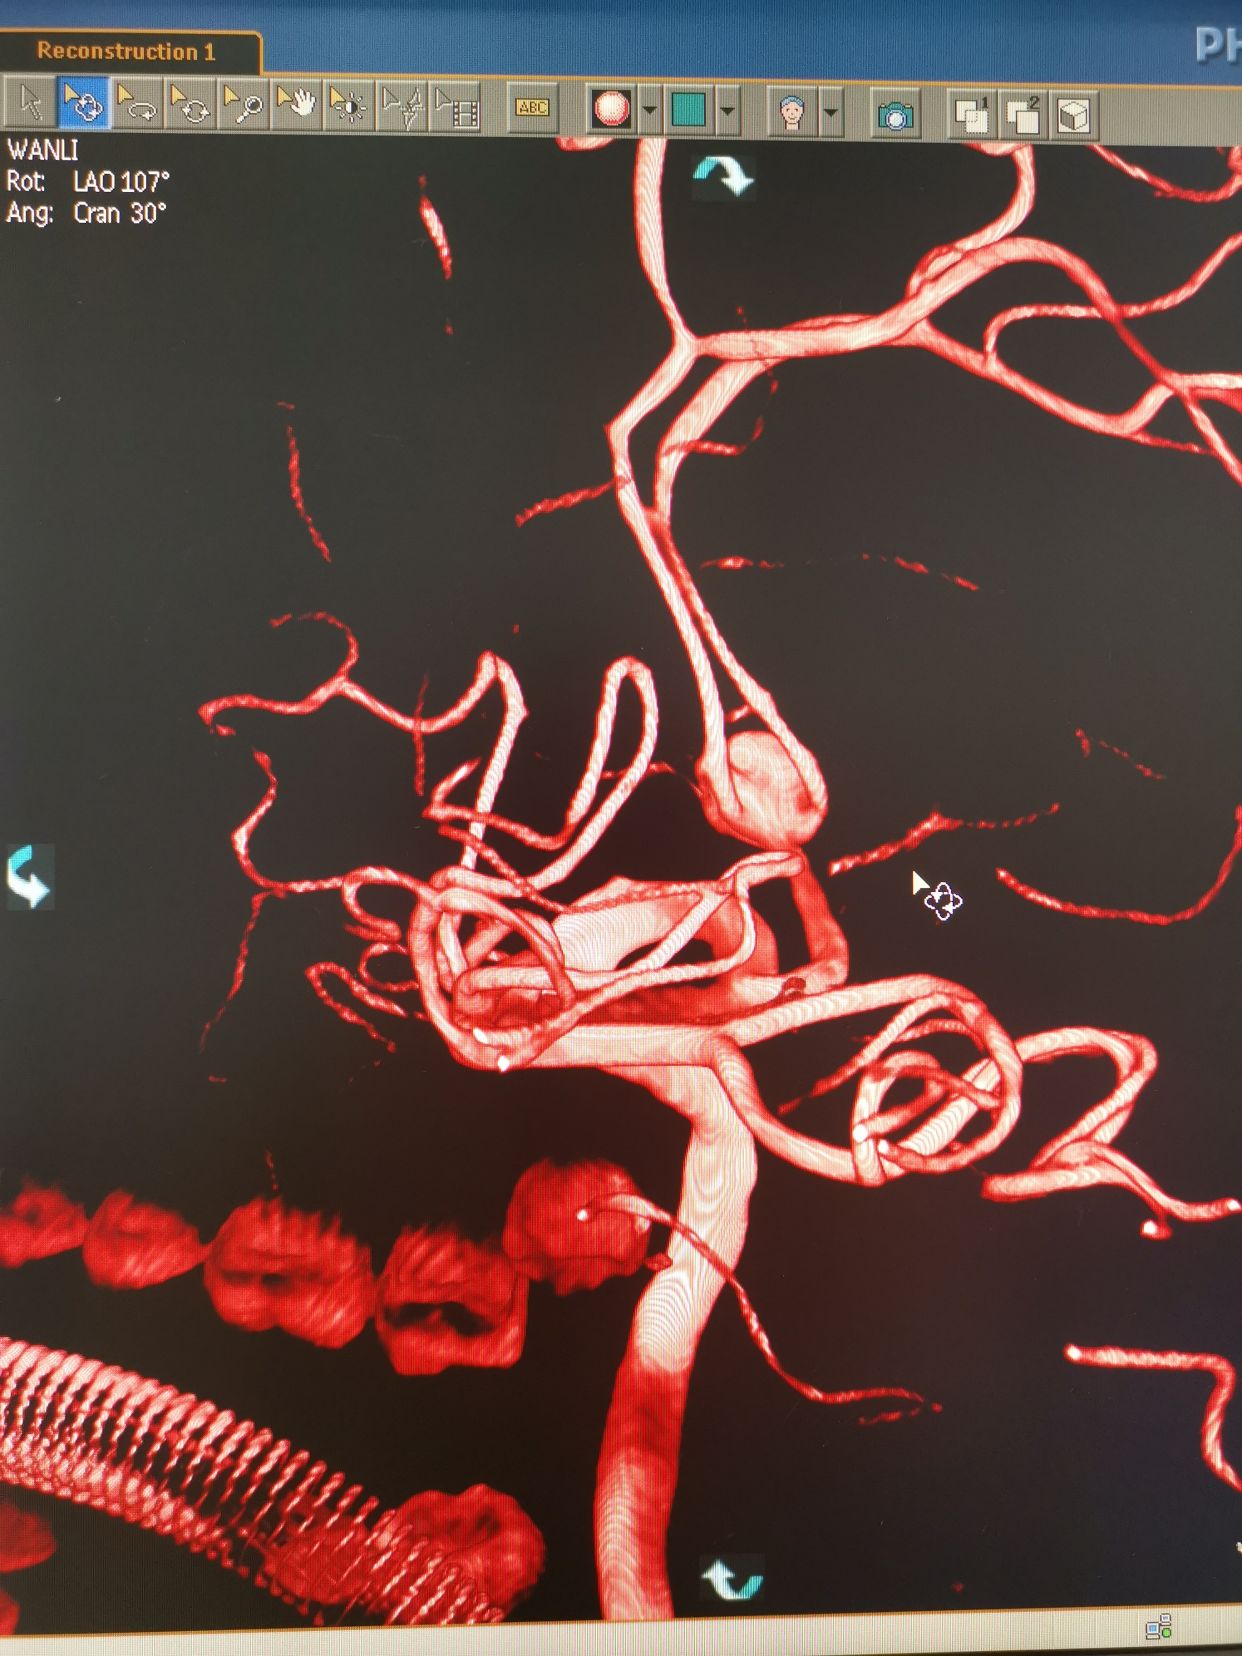

造影过程中,患者出现意识障碍加深,烦躁,不能配合,考虑颅内出的增加可能。术中请麻醉科老师急诊行气管插管麻醉。后行左侧颈内动脉3D造影。

左侧颈内动脉3D